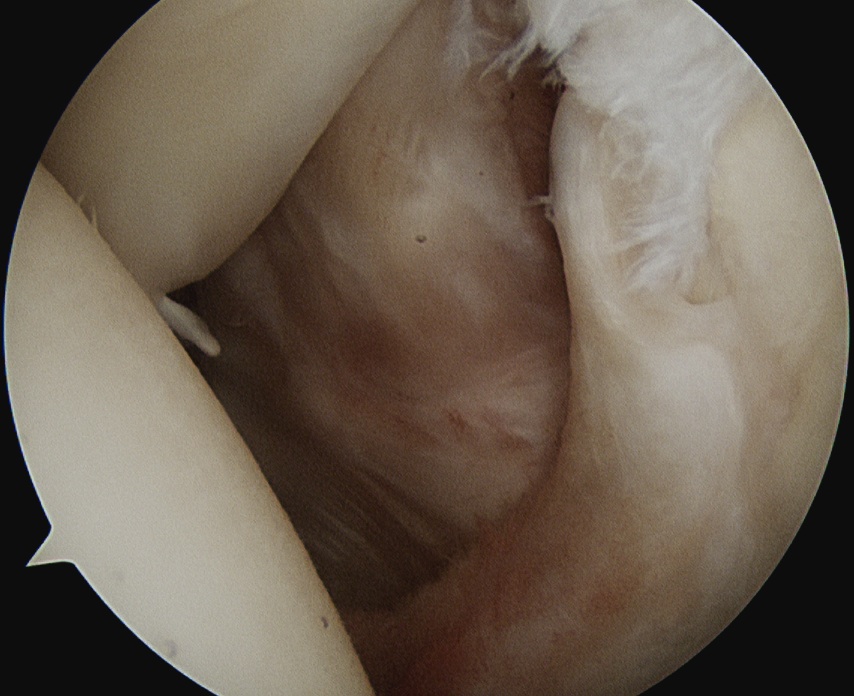

Comma sign

- medially retracted subscapularis tear

- exposes the superior insertion of superior glenohumeral ligament / coracohumeral ligament

Full thickness retracted subscapularis tear with comma sign